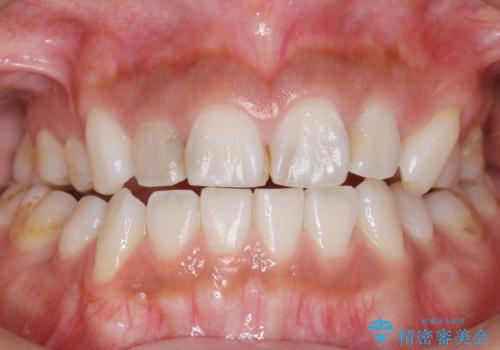

- 上の前歯の色と隙間を気にされ、来院された患者様です。

精査したところ、右上の側切歯(右上2)は神経が死んで変色しており、左上の側切歯と犬歯の間に2mm程度の隙間を認めました。

矯正せずに早く治したいという強いご希望により、セラミッククラウンによる補綴治療(上顎両側2の2本)を行いました。